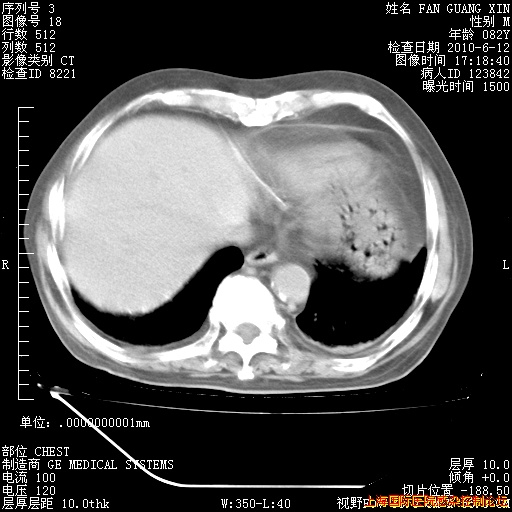

补发6月12日肺部CT肺窗

6月12日肺窗

整整相隔30天的肺部CT好像有所好转啊。甲强龙减量第3天,需要观察体温。

海管,自昨日你和我通完话后,不知您岳父消化道症状有无缓解?体温怎样?阅读7.12日胸部ct,个人认为目前激素治疗是有效的,甲强龙减量是适宜的。因在抗痨治疗,需密切观察肝功、肾功能和血常规。不过,老年、长期住院和大量使用激素,很担心菌群失调发生